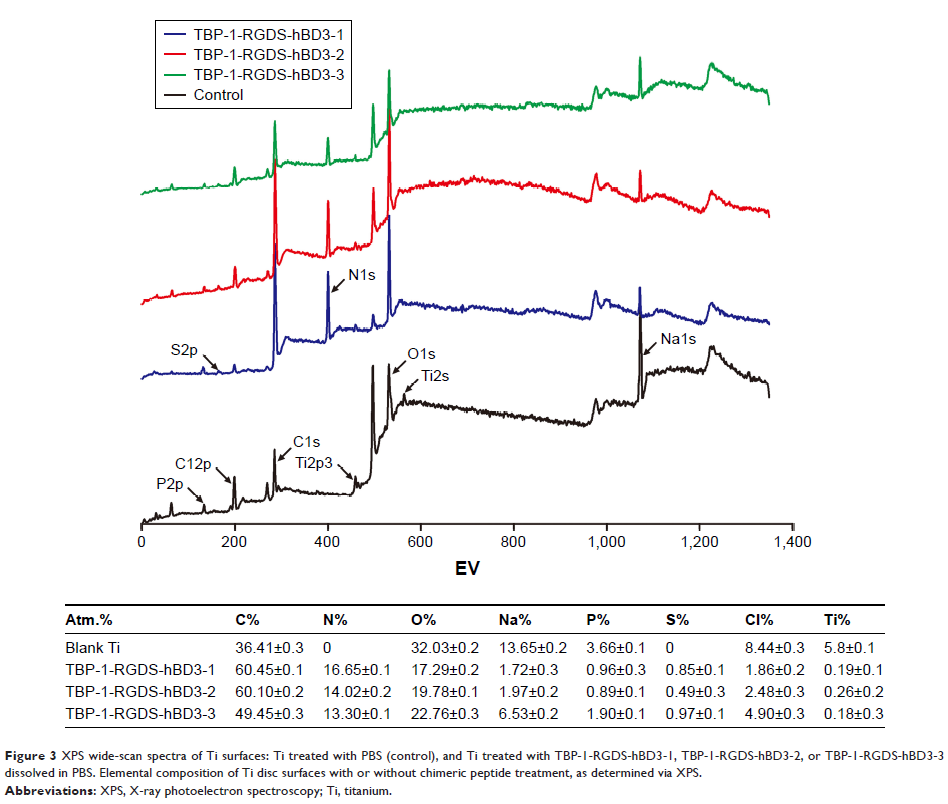

Original Research

用多功能嵌合肽修饰钛表面以通过抑制初始定殖器来防止生物膜形成

- 作者:Xi Zhang, Hongjuan Geng, Lei Gong, Qian Zhang, Hongjie Li, Xu Zhang, Yonglan Wang, Ping Gao

- 期刊:International Journal of Nanomedicine